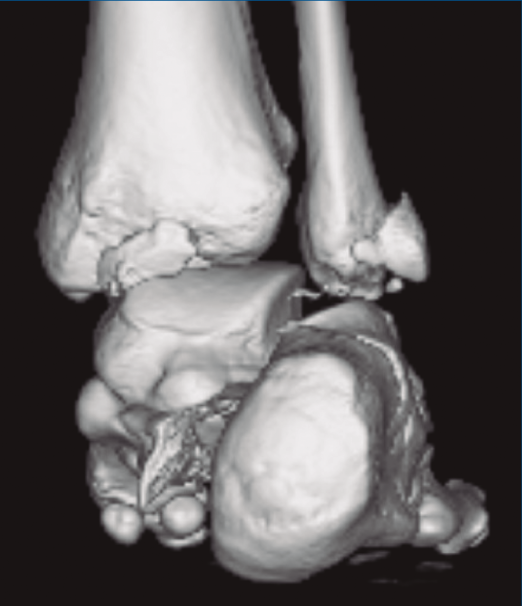

Se trata de un varón de 19 años que ingresa en reanimación tras precipitarse desde una altura de aproximadamente 10 metros. El paciente presenta una fractura estallido de L3 con afectación del canal medular junto con una fractura del vértice inferior de L4, así como una fractura luxación de calcáneo, asociada a una fractura del maléolo peroneo y del maléolo tibial posterior (Figuras 1 a 6) diagnosticadas mediante TC total body (por eso no se dispone de radiografías simples al momento del ingreso). Como podemos comprobar, se trata de una fractura de doble trazo de tipo hundimiento/depresión de la carilla articular (Figuras 5 y 6).

Figura 4. Luxación fragmento posterolateral.

Figura 5. Fractura maléolo peroneo, luxación astrágalo, fractura de doble trazo en calcáneo.

Figura 6. Fractura de doble trazo; se evidencia afectación de la articulación calcaneocuboidea.

A su llegada a urgencias, se inmovilizó con férula posterior de yeso tras no conseguirse la reducción cerrada (Figuras 7 y 8). Debido a la patología asociada, subsidiaria de tratamiento quirúrgico de urgencias (artrodesis de L2 a L4 con tornillos transpediculares, por parte de neurocirugía), se decide demorar eñ tratamiento definitivo de la fractura luxación de calcáneo 2 semanas, hasta conseguir una mejoría en el estado de las partes blandas.